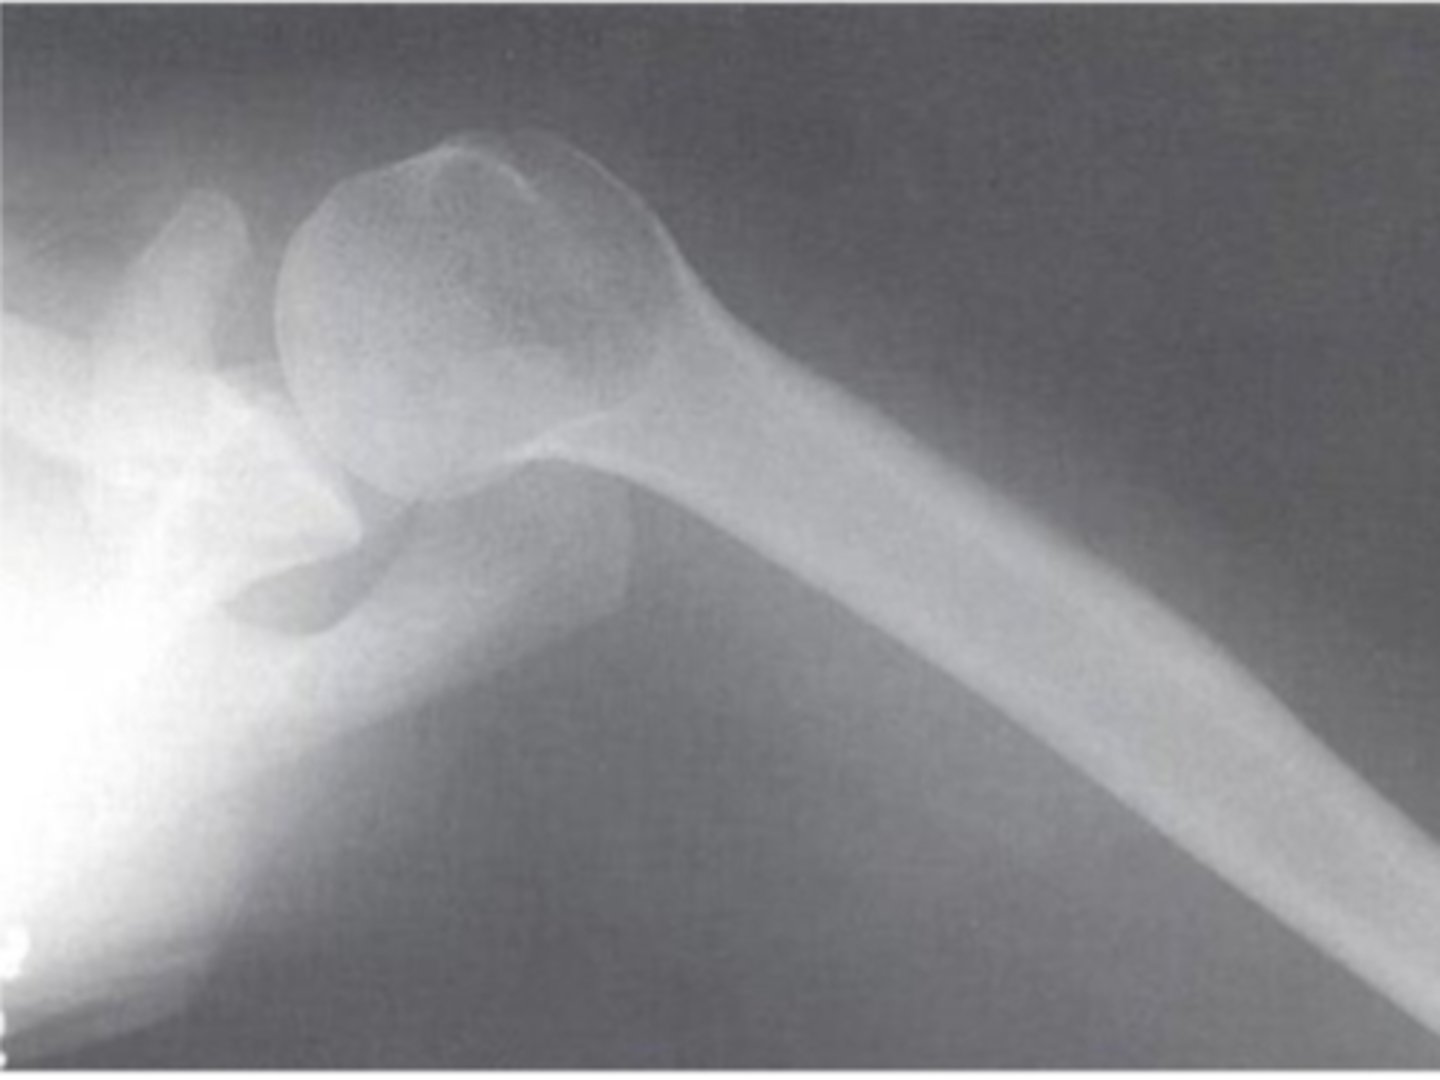

Axillary alignment of the glenohumeral joint

What view does this show?